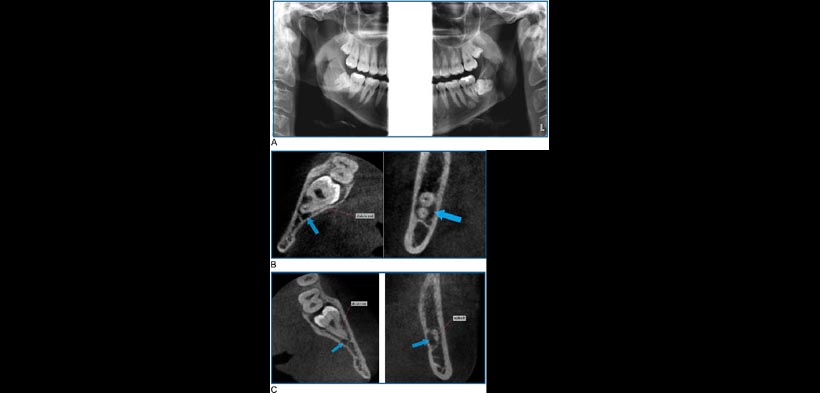

Figura 1 (A) segmentado de la imagen panorámica de las dos terceras molares inferiores. La interrupción de la cortical superior del canal mandibular está presente en ambos lados. (B) cortes axiales y coronales del tercer molar inferior derecho muestra ausencia de cortical se separación ósea entre las raíces del tercer molar y el canal mandibular. Las flechas indican el canal mandibular. (C) cortes axiales y coronales del tercer molar inferior izquierdo que muestra ausencia de cortical de separación ósea entre las raíces del tercer molar y el canal mandibular. Las flechas indican el canal mandibular.